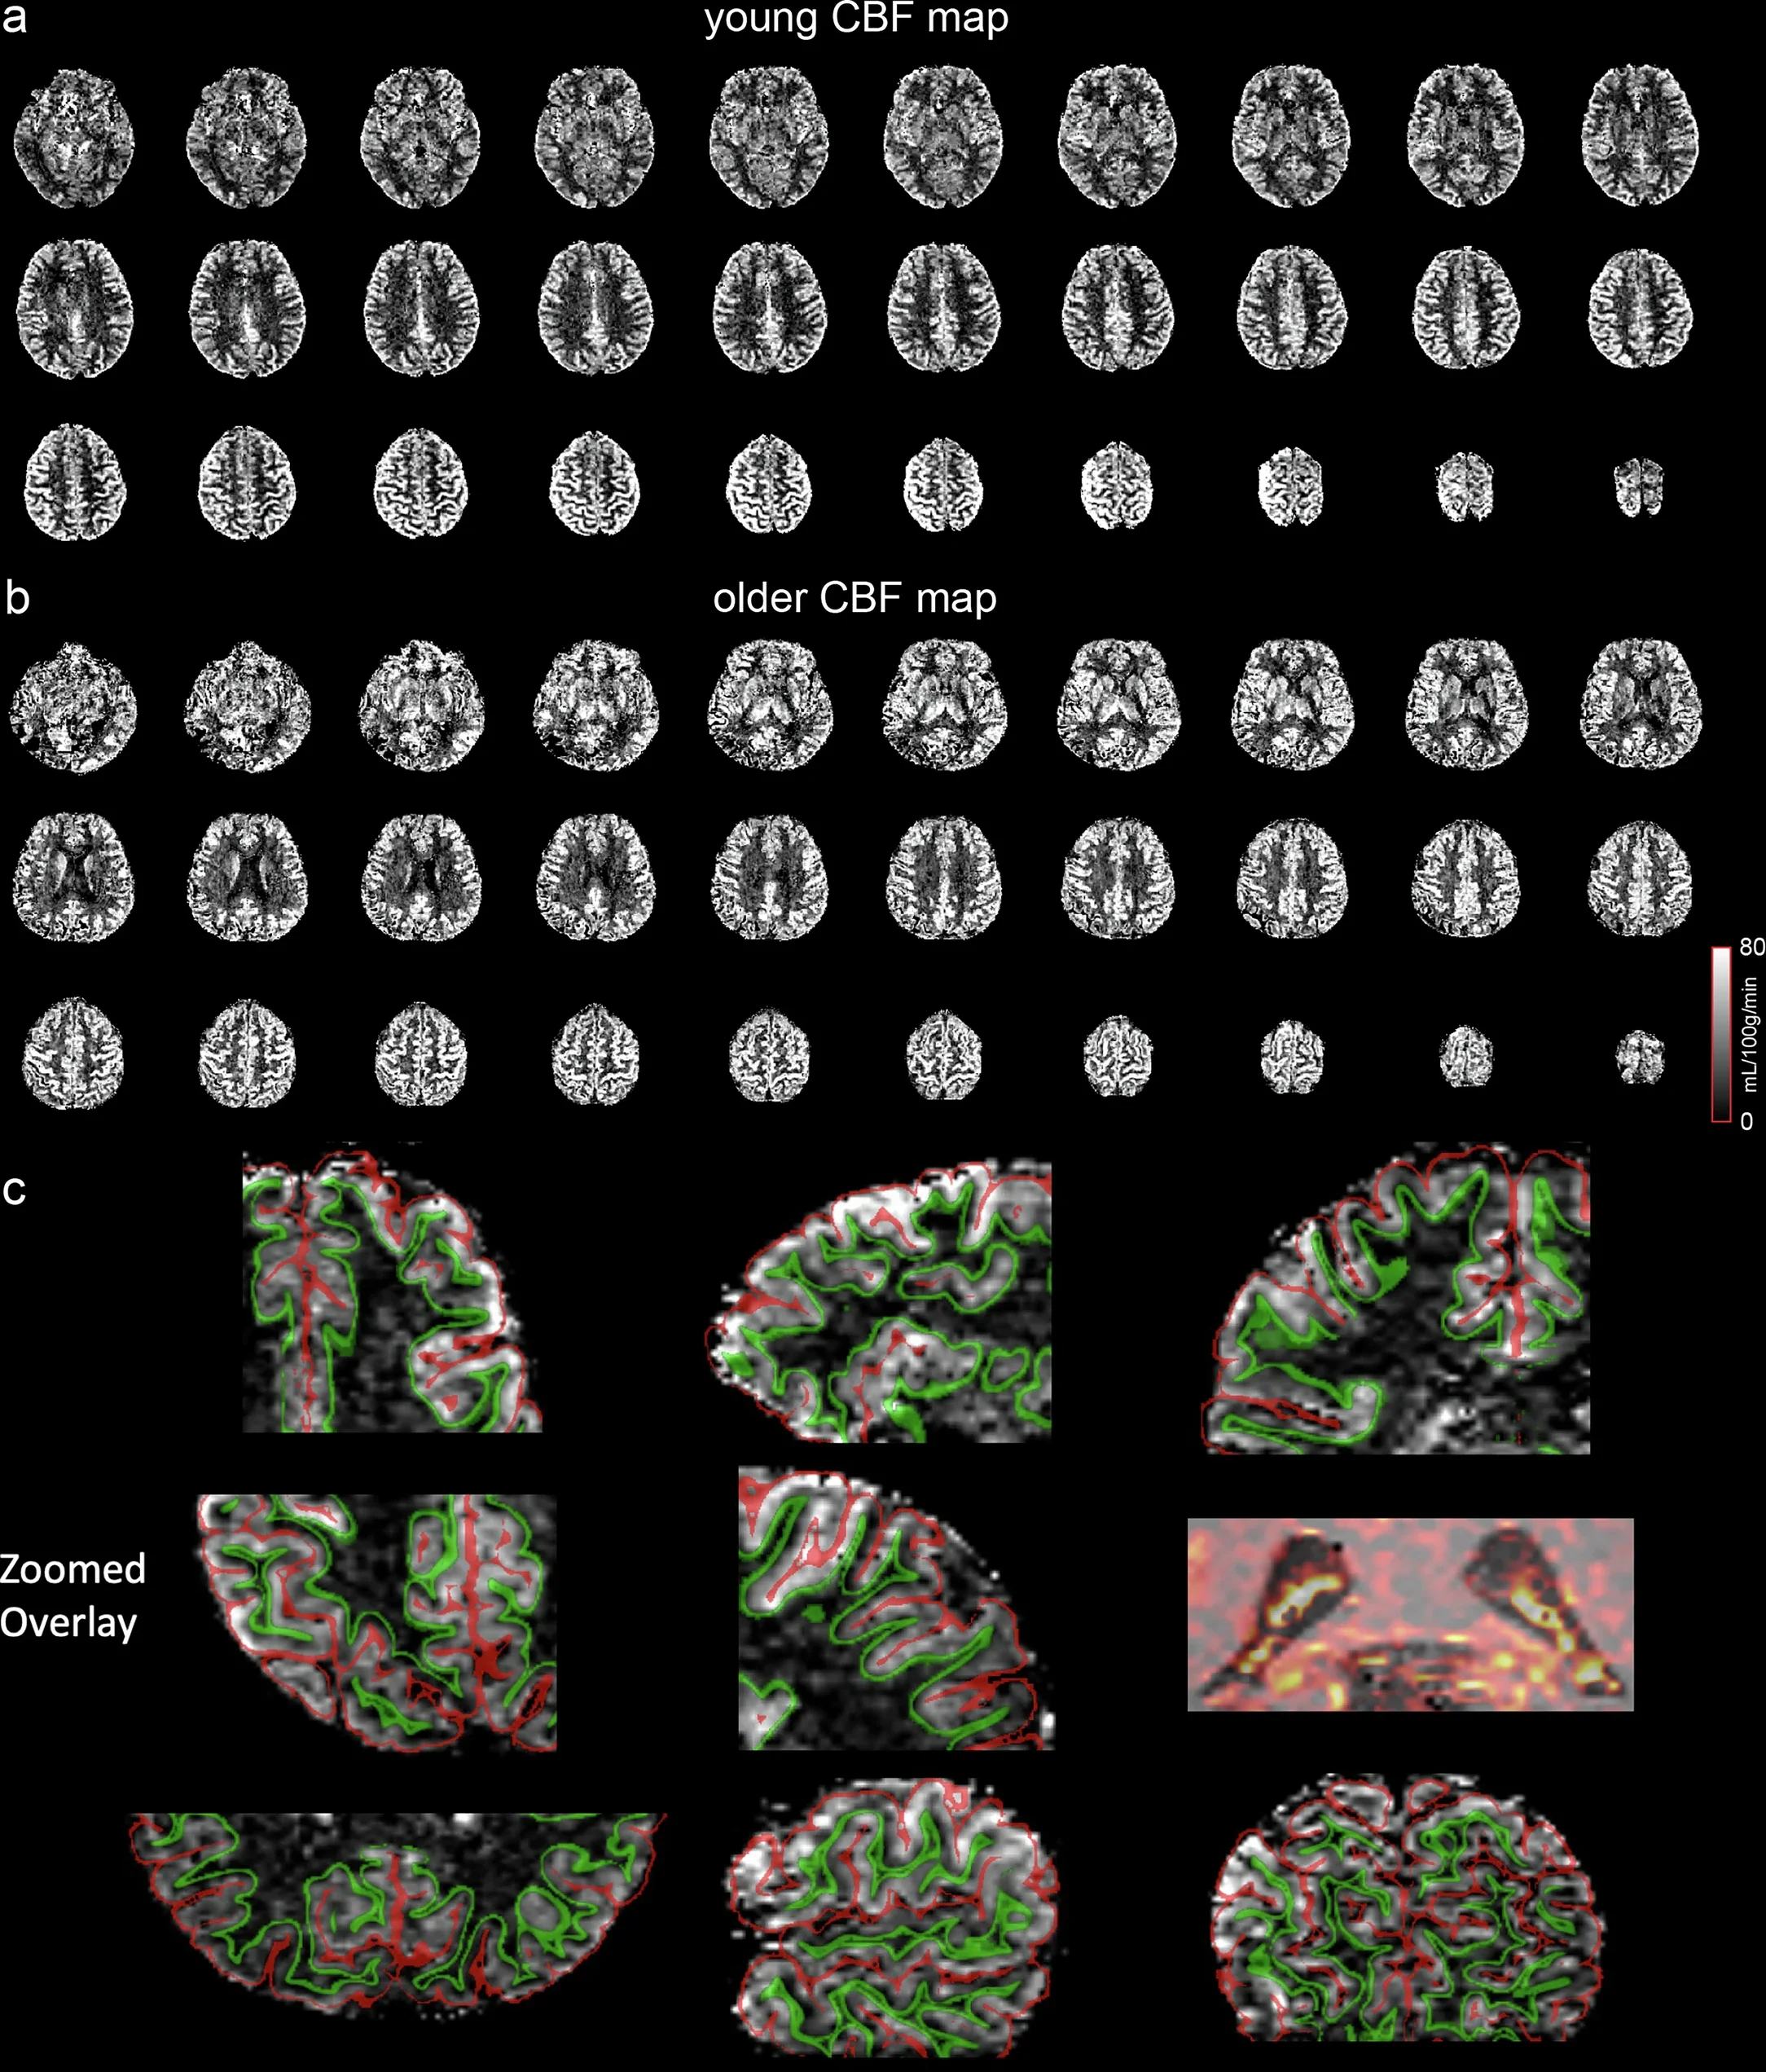

Mapas de flujo sanguíneo cerebral (CBF) obtenidos con resonancia magnética de alta resolución. (a) Participante joven. (b) Participante mayor. (c) Ampliaciones con superposición de segmentación. La calidad y especificidad espacial de estas imágenes permiten un análisis detallado por capas corticales y una visualización precisa del plexo coroideo, donde se observa una alta distribución del flujo sanguíneo. Cortesía: Guo, F., Zhao, C., Shou, Q. et al.